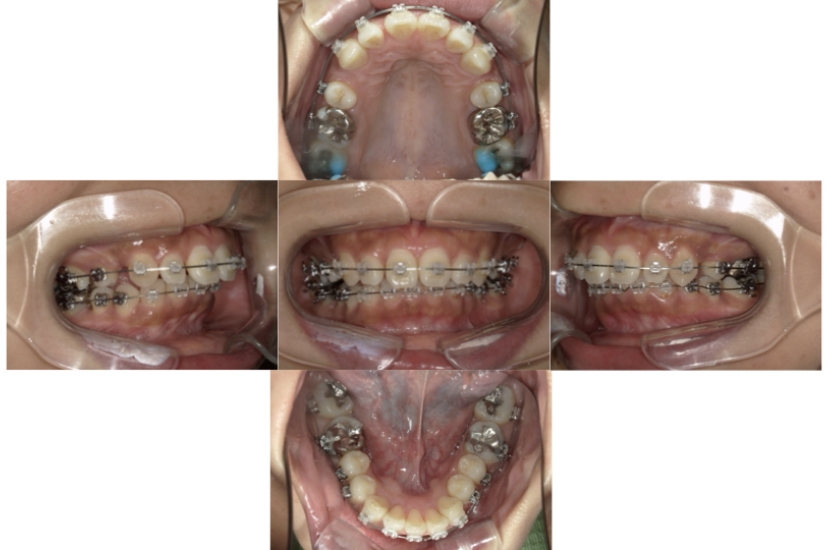

症例8

叢生

抜歯

ブラケット矯正

上下顎叢生(上下の前歯のガタガタ)のケースです。

装置はラビアル(上下表側)で、上下顎の小臼歯を4本抜歯を行っています。抜歯したスペースを使って、上下の前歯の後方移動と叢生(ガタガタ)の改善を行っています。

主訴 歯並びが悪く、舌を噛んでしまうのを治したい。

年齢・性別 27歳 男性

お住まいの地域 東京都大田区

治療方針 抜歯スペースを利用して上下前歯の叢生(ガタガタ)の改善

抜歯部位 上下顎左右第一小臼歯

使用装置 ラビアル(上下表側)、顎間ゴム

治療期間 3年1か月

治療回数 30回

リテーナー クリアリテーナー

AFTER